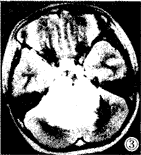

图1-3 女性,5岁,脑干明显增大膨突,横断面T1W低信号(图1),T2W高信号(图3),无明显强化(图2),肿块向前包绕基底动脉,向后推移第四脑室。图4-6 女性,6岁,横断面T1W低信号(图4),矢状面T1W增强(图5), 横断面T1W增强(图6),片状不均匀强化灶中见结节样强化。图7 男 性,6岁,横断面T1W增强,肿块环状强化呈葫芦形,中央低信号灶不强化。图8 女性,2岁,矢状面T2W,肿块向后压迫中脑导水管,第三脑室、侧脑室积水明显。

MRI:鉴于无颅骨伪影和多方位成像特点,MR是目前诊断胶质瘤和准确定位的最好方法,对于治疗计划的制定和随访有很大帮助,特征性MR表现为脑干胶质瘤呈膨胀性生长(图1~3),多为实质性,在T2加权图像上显示最为清楚,为明显高信号(图3),在T1加权图像上为低信号或低、等混合信号(图4),注射GD-DTPA后多数病灶 明显增强,少数无明显增强(图1~2),强化方式有:弥漫型(图未列出)、结节型(图4 ~6),沿着肿瘤边缘或囊变坏死区呈环状(图7)。肿瘤边界多较清楚,周围脑组织水肿多 较轻或不明显,肿瘤内部可发生小囊变或小出血灶,肿瘤向前生长包埋基底动脉(图1~3) ,部分脑干胶质瘤可位于中脑导水管附近,虽然较小,但可造成对中脑导水管的压迫,而继 发脑积水[3](图8),MRI较CT能更好地明确占位性病变的性质、部位、范围。